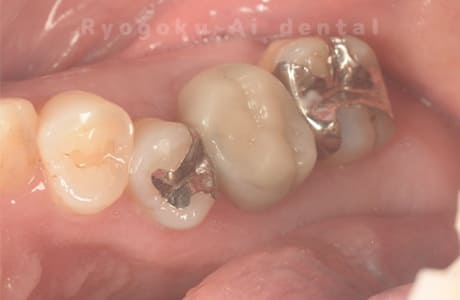

Case07

- 慢性根尖性歯周炎(16・17・15部)

- 治療内容

- マイクロエンド(3歯分)

- 308,000円(3歯分)※被せ物を除く

右上の違和感が取れないとのことで来院された患者さんです。ファイルという器具が歯の根の中で折れていることを説明し、マイクロスコープを使用した根管治療を提案し、治療を行いました。折れたファイルも取り除くことができ、現在の経過は良好です。